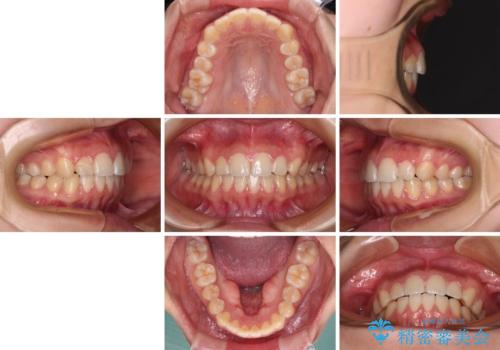

カリエールディスタライザーを併用したことで、確実かつ短期間で治療を終えることができました。